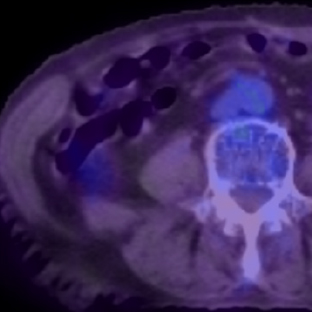

a. 心臓CT

SPECT/CT融合画像

図3 労作性狭心症症例。後側壁〜後下壁の心筋虚血はLCXおよびRCA両方の有意狭窄による。